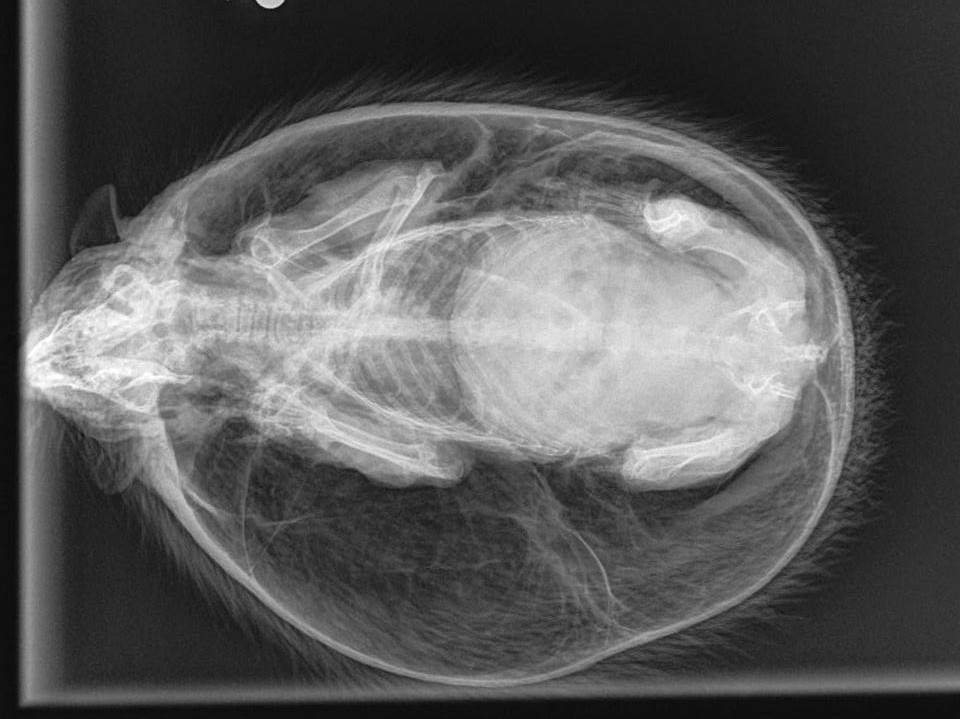

Con nhóm nặng 1kg được giải cứu vì tưởng đang mang thai. Hình ảnh chụp X-quang cho thấy nó bị một hội chứng hiếm gặp. Hội chứng bong bóng khiến cơ thể nở phồng gấp đôi bình thường.

Ảnh chụp X quang con nhím

"Đây là trường hợp tồi tệ nhất của hội chứng bong bóng mà tôi từng nhìn thấy", Dransfield nói.

"Con nhím này phình to gần gấp đôi kích cỡ tự nhiên của nó, nở phồng như một quả bóng bãi biển. Tôi đưa con vật đến Sheffield, nơi nó được chụp X quang và thả một ít không khí ra khỏi cơ thể”.